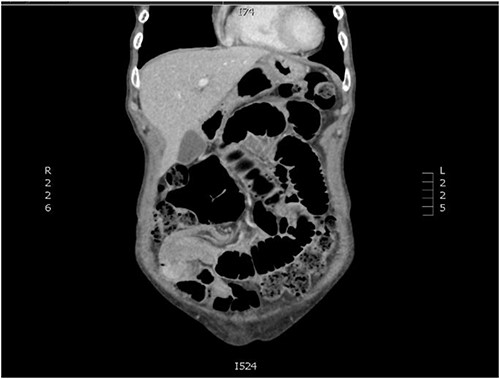

An independent 75-year-old woman presented to the emergency department with a 1-day history of crampy abdominal pain, nausea, vomiting and constipation. Her medical history includes multiple myeloma, which has been in remission for 4 years. She has no surgical history. On examination, she was alert but distressed with the pain. She was afebrile, normotensive and saturating well on room air with a regular pulse of 110, suggesting sinus tachycardia. Abdominal examination demonstrated a distended abdomen with tenderness around the umbilicus. There were no obvious hernias, and the rest of the abdominal exam was unremarkable. Her haematological investigations were unremarkable, and she had a lactate of 0.9 mmol/L. A computed tomography (CT) of her abdomen and pelvis with intravenous contrast was performed to investigate the cause of her pain. It demonstrated a partial or intermittent mid small bowel obstruction secondary to an intussusception (Figs 1 and 2).

Coronal slice of CT abdomen and pelvis showing an intussusception.